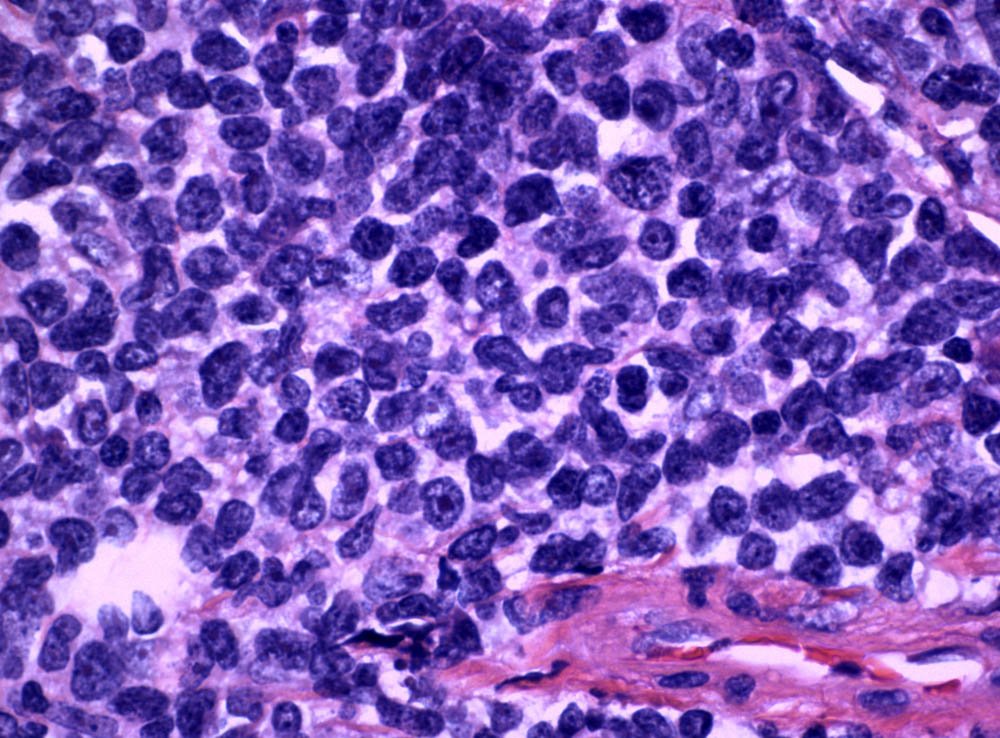

Case: AxillaryMass

Specials to Order:

Final Diagnosis: